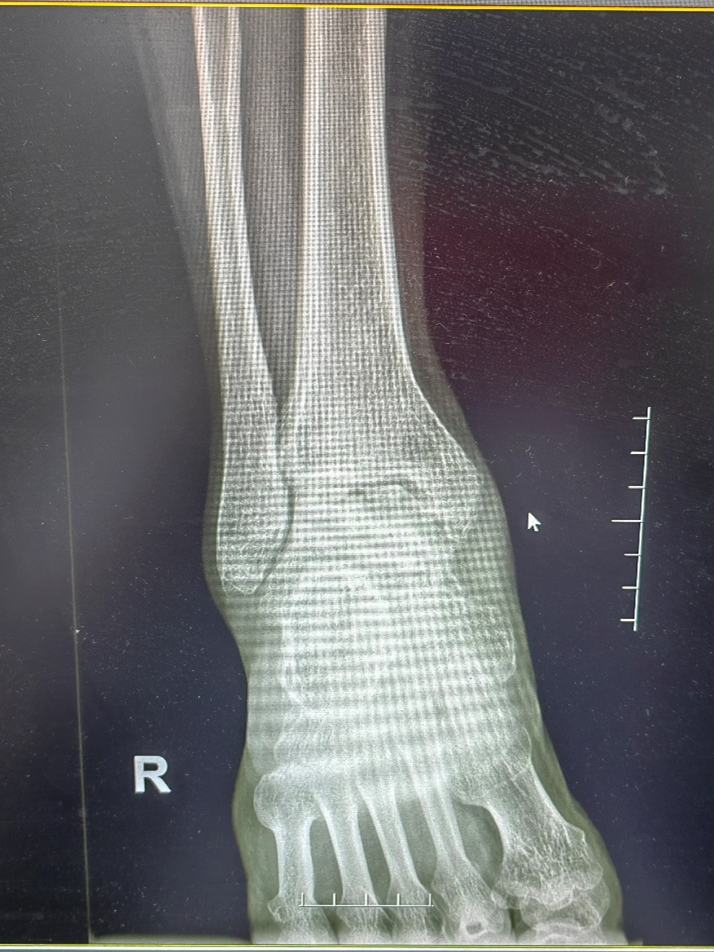

X线检查可见患者出现右踝关节退变,距骨坏死